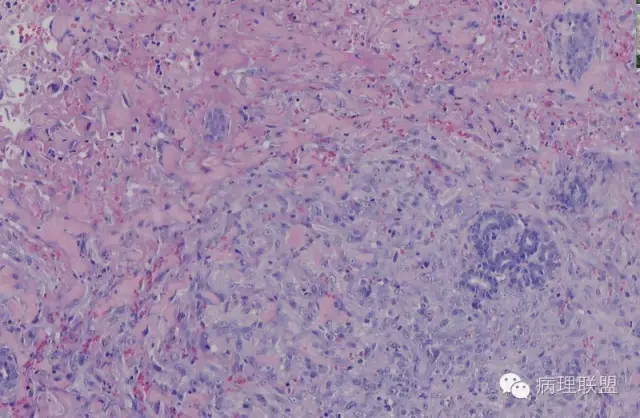

血管裂隙样,弯曲排列,似迷宫样,良性应该打不住,需往中间型考虑,请大咖们指点,软组织的重点应该放在良恶性的鉴别吧。

@南方医科大学病理梁莉 形态较符合复合性血管内皮瘤(composite hemangioendothelioma),属中间性血管性肿瘤。此肿瘤尽管多见于成人,也可发生于婴幼儿。

这例我们发的是卡波西样血管内皮细胞瘤,考虑如下:(1)新生儿,肢体肿物;(2)位置深,侵及皮下脂肪;(3)大多是裂隙状血管,也有少量吻合的血管网,细胞有异形,可见坏死

Kaposi型血管内皮瘤常有隐约小叶结构,梭形细胞束间有毛细血管,细胞核异型性和分裂活性一般不明显,常见梭形细胞束和圆形"肾小球样"实性细胞巢混合存在。

有些区域类似Kaposi肉瘤,如下图

而复合性血管内皮瘤则是由良性、中间性和恶性的成份组成,也是浸润性生长,常常侵犯皮下脂肪组织,此例细胞形态由梭形细胞、卵圆形细胞及上皮样细胞组成,形态可见良性区域、中间性区域及高分化血管肉瘤或上皮样血管肉瘤区域,因此,似乎复合性血管内皮瘤更妥。此类肿瘤可以发生于婴幼儿。当然与Kaposi型血管内皮瘤一样,同属中间性血管瘤,只是后者,若肿瘤体积大,可出现Kasabach-Merritt综合征。